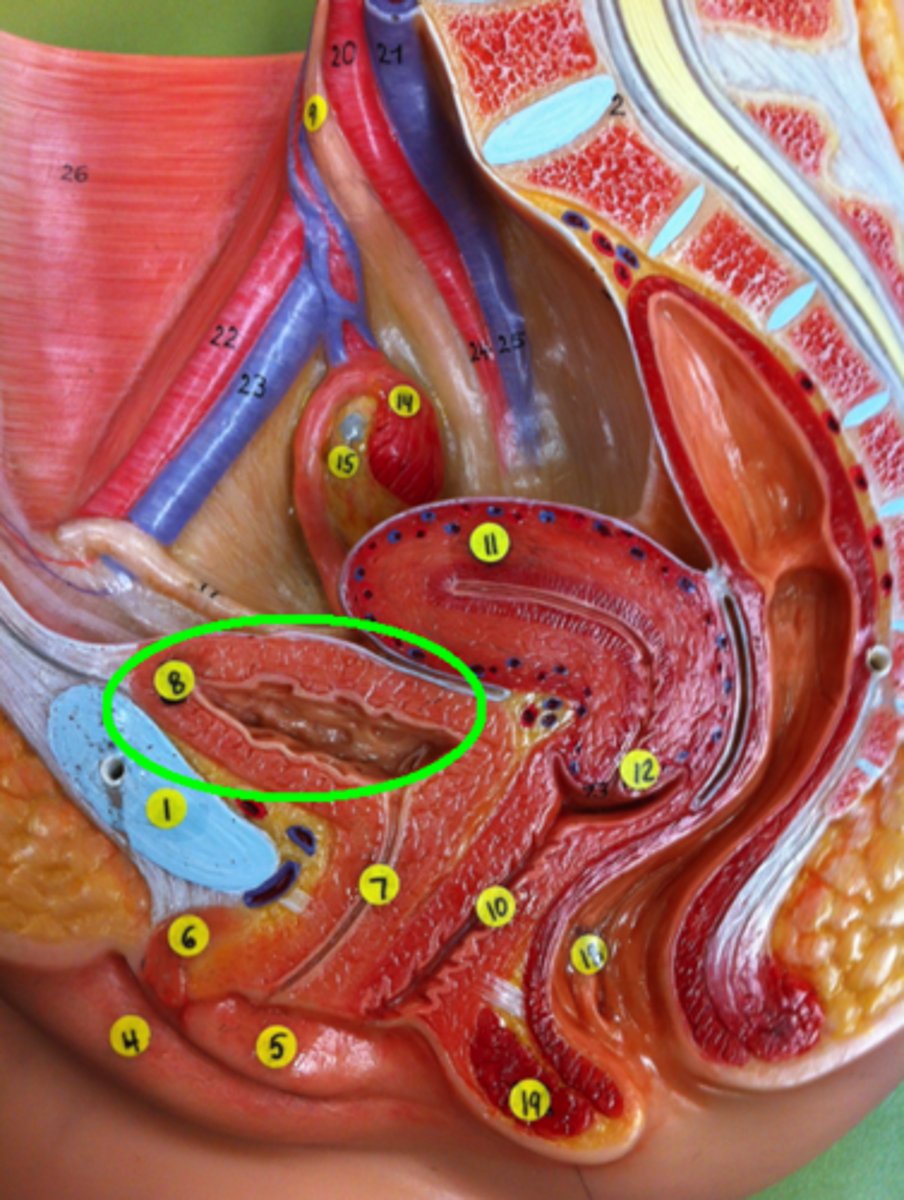

Vagina